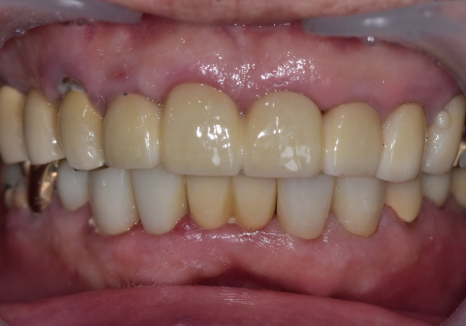

240502

보철물을 올릴 때는

음식물이 최대한 끼지 않도록

정밀하게 설계하는 데 집중했습니다.

크라운 세팅 시에는 치간 칫솔 사용법을

상세히 설명해 드리며

관리 방법도 잊지 않고 안내해 드렸어요~

240711

치료가 마무리된 후의 모습입니다.

검게 변색되었던 부분들이 사라지고

인상이 전체적으로 깨끗하고 단정해 보이네요.^^

240223(전) 240711(후)